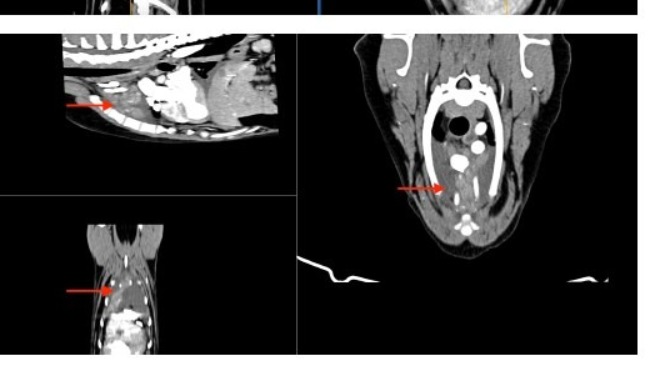

Przed nami biopsja guza w klatce piersiowej. Guz nie reaguje na chemię i jest podejrzenie, że może to być druga choroba.

Chłoniak jest w częściowej remisji. Pozostaje płyn w jamie opłucnej oraz guz w śródpiersiu, który będzie diagnozowany. Kontynuacja leczenia za dwa tygodnie.

We wrześniu 2025 badania profilaktyczne wykazały duże nieprawidłowości w organizmie Atenki. Pomimo początkowych wątpliwości kompleksowe badania potwierdziły chłoniaka T-komórkowego, tego bardziej agresywnego.